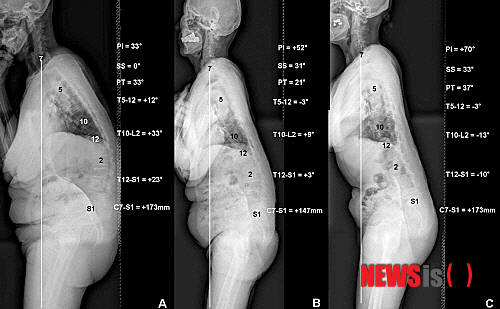

【서울=뉴시스헬스/뉴시스】골반입사각에 따라 퇴행성요추후만증의 추이가 달라지는 양상을 보인다. (사진=우리들병원 제공) 이새하 기자 lovesaeha@newsishealth.com

【서울=뉴시스헬스/뉴시스】 개인마다 다른 골반 입사각이 허리가 뒤로 굽는 퇴행성요추후만증 진행의 주요 변인이라는 연구결과가 나왔다.

논문에서는 퇴행성요추후만증 환자 172명과 건강한 성인 39명을 골반 입사각에 따라 세 그룹으로 나누고 골반 입사각, 천추 경사각, 골반 경사각, 요추 전만부, 시상 수직축 등 척추-골반 지표들의 연관관계를 비교 연구했다.

그 결과 골반 입사각이 큰 그룹은 요추 전만각이 비교적 유지됨에도 불구하고 골반 신전근의 약화로 척추 모양이 앞으로 굽는 시상불균형으로 진행됐다.

반면 골반 입사각이 작은 그룹은 요추 후만증과 함께 등-허리의 후만증도 함께 진행하며 척추 모양이 앞으로 굽는 시상불균형으로 진행된 것으로 나타났다.

골반 입사각은 각 환자마다 교정 후의 바람직한 척추-골반 모양을 예측할 수 있게 해 척추변형을 치료에 가장 중요한 해부학적 지표다.